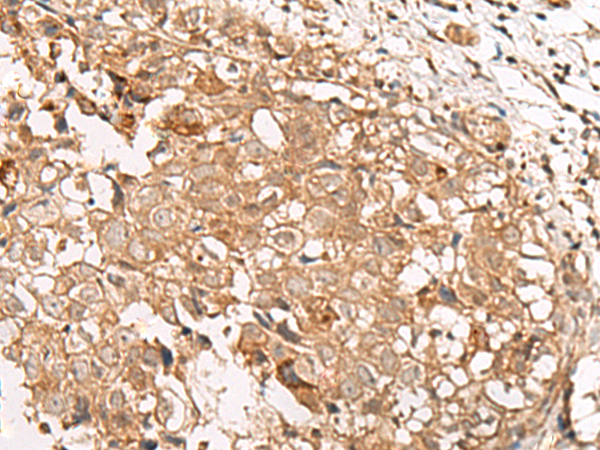

(The image is immunohistochemistry of paraffin-embedded Human lung cancer tissue using 47570(GBGT1 Antibody) at dilution 1/20.(Original magnification: 200))